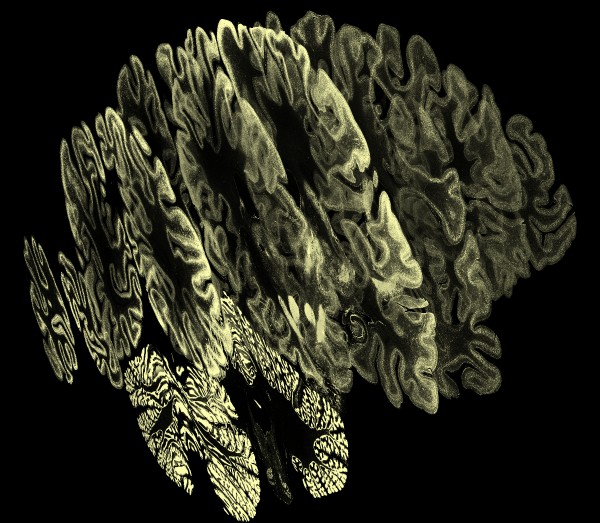

| Slices (20 um)

| Slice

- Show ortho-plane slices of 100 um or 400 um brain.

- Show 20 um single plane zoomed in to pixel size.

- Show a traced neuron superimposed on 20 um plane.

- Show 500 traced neurons at 10x normal spacing.

- Show 500 neurons at normal spacing, densely packed.